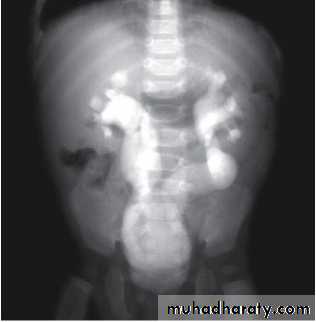

Grading of VUR

The degree of reflux is graded I–V.

Grading is based on the appearance of contrast agent in the collecting system during voiding cystourethrography (VCUG(.

DMSA scan to detect and monitor associated renal cortical scarring.

The intravenous urography (IVU) findings are usually normal in lower grades of reflux.